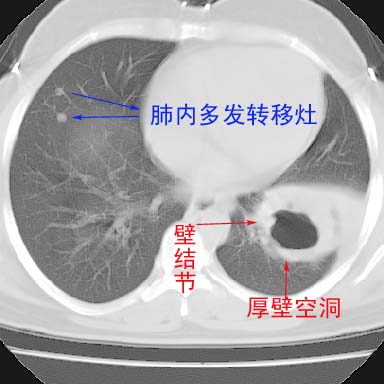

左下肺肿块影,内可以见小泡征,并见厚壁空洞形成,洞内缘凹凸不平,可见壁结节。靠近胸膜侧可见胸膜凹陷征。左侧胸腔内可见少量低密度积液影。右肺可见两处高致密的小结节影。

考虑:左下肺周围型肺癌伴右肺转移

左下肺肿块影,内可以见小泡征,并见厚壁空洞形成,洞内缘凹凸不平,可见壁结节。靠近胸膜侧可见胸膜凹陷征。左侧胸腔内可见少量低密度积液影。双肺可见多发性小结节影。

考虑:左下肺癌性空洞伴两肺转移

左下肺肿块影,内可以见小泡征,并见厚壁空洞形成,洞内缘可见壁结节。靠近胸膜侧可见胸膜肥厚粘连。双肺可见多发性小结节影。

考虑:左下空洞性肺癌伴两肺转移

偏心性厚壁空洞,壁结节,胸膜肥厚粘连,双肺多发性小结节灶。这么多典型征象,即使错了也错的有道理!

左下肺有空洞,壁厚薄不均,壁结节,两肺多发小结节影,腋窝下可疑淋巴结肿大,综上所述考虑周围性肺癌并两肺转移可能性大,建议穿刺活检。

右肺多发小结节影,边界清楚,符合转移瘤的特点;2、左下肺偏心性空洞影,右侧乳腺内高密度影,需要查体除外右侧乳腺肿瘤;3、腋窝淋巴结肿大,考虑转移。

支持癌性空洞:壁厚,无液平,内壁不规则,外壁呈分叶状,较大,偏心性,壁结节,胸膜凹陷,转移灶。